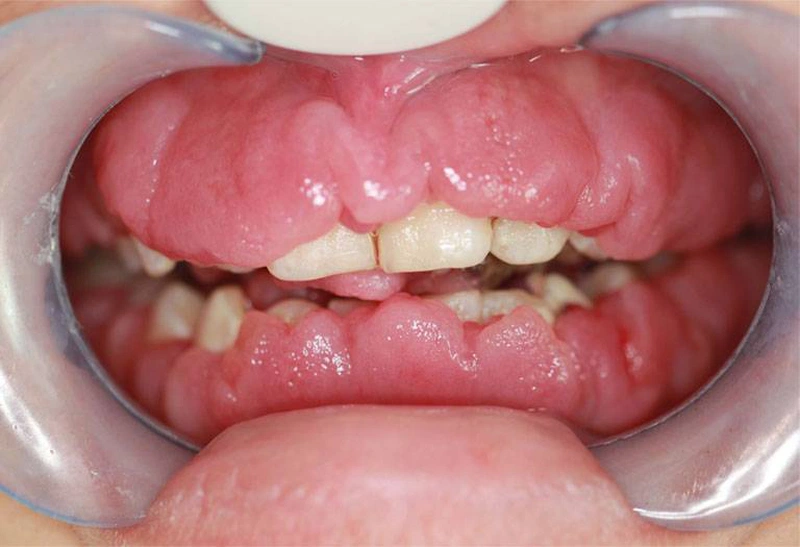

Viêm lợi phì đại là một tình trạng bệnh lý đặc trưng bởi sự tăng sinh quá mức của mô nướu. Từ đó dẫn đến hiện tượng nướu dày lên, sưng nề và có thể bao phủ một phần thân răng. Hiện tượng này thường là kết quả của phản ứng phì đại của mô lợi. Phản ứng này xảy ra đối với các tác nhân kích thích tại chỗ. Phổ biến nhất là mảng bám vi khuẩn còn mắc trong kẽ rằn. Đây là một yếu tố nguy cơ hàng đầu trong các bệnh lý nha chu.

Ngoài ra, tình trạng này cũng có thể phát sinh do tác dụng phụ của một số loại thuốc. Đặc biệt là các nhóm thuốc như thuốc chống động kinh (ví dụ: phenytoin). Ngoài ra là thuốc ức chế miễn dịch (cyclosporin), thuốc chẹn kênh canxi (như nifedipine). Tình trạng phì đại mô nướu không chỉ gây ảnh hưởng nghiêm trọng đến yếu tố thẩm mỹ. Điều này thể hiện qua việc nó làm cho răng trông ngắn hơn. Thậm chí khiến nướu chuyển sang màu đỏ đậm hoặc tím tái. Nó còn tác động tiêu cực đến chức năng sinh lý của khoang miệng.

Tăng sản nướu có yếu tố di truyền, hay còn gọi là u xơ nướu di truyền, là một nguyên nhân đặc biệt dẫn đến viêm lợi phì đại. Đây là tình trạng mô liên kết của nướu phát triển quá mức do đột biến gen. Điều này thường xuất hiện từ giai đoạn mọc răng sữa. Thậm chí có thể kéo dài đến khi hoàn thiện hàm răng vĩnh viễn.

Ở giai đoạn đầu, u xơ nướu có thể không gây triệu chứng đau đớn rõ rệt. Điều này khiến người bệnh và phụ huynh khó nhận biết. Tuy nhiên, nếu không điều trị sớm, mô nướu sẽ dần bao phủ thân răng. Từ đó gây cản trở nghiêm trọng đến chức năng ăn nhai, phát âm. Cùng với đó là vệ sinh răng miệng và cả sinh hoạt hàng ngày. Trong một số trường hợp nặng, can thiệp phẫu thuật nướu là cần thiết. Thông qua đó phục hồi chức năng và thẩm mỹ.